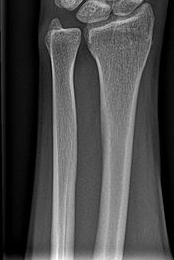

ПЕРЕЛОМ ЯКОЇ КІСТКИ І ЯКОЇ ЇЇ ЧАСТИНИ ВИ БАЧИТЕ НА РИСУНКУ?

варіанти відповідей

ДИСТАЛЬНОГО ДІАФІЗА

HUMERUS

ULNA

RADIUS

ПРОКСИМАЛЬНОГО ЕПІФІЗА

ДИСТАЛЬНОГО ЕПІФІЗА

ДІАФІЗА

МЕТАФІЗА